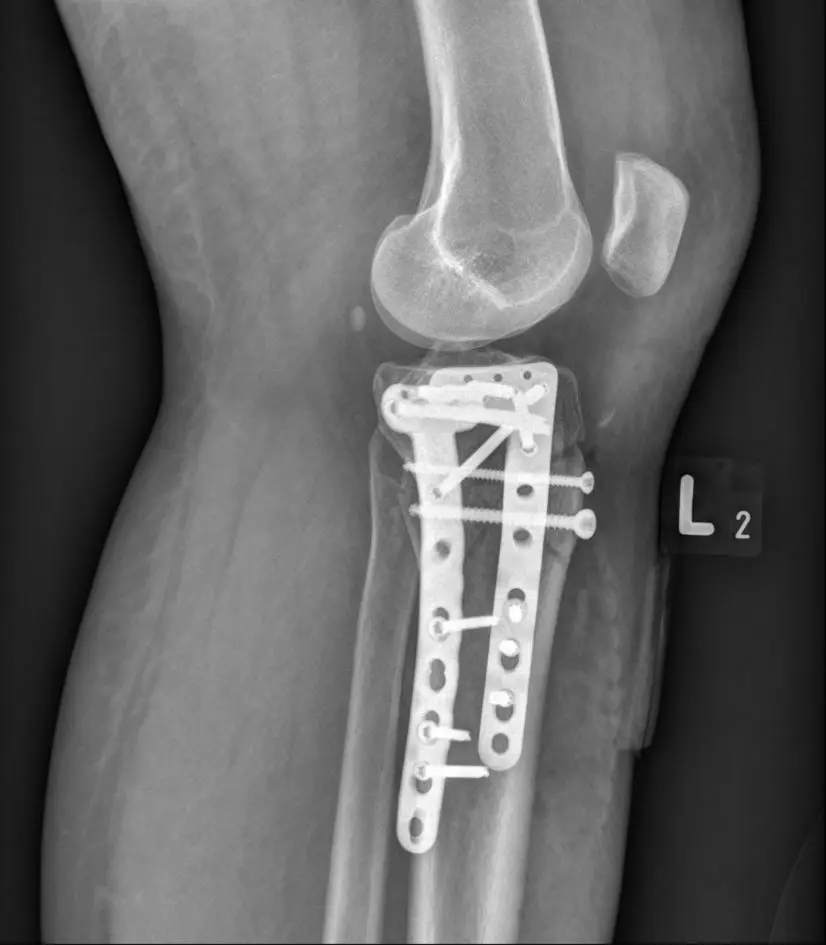

X-RAY: Stabilization of the proximal end of the tibia fracture after an accident

Fractures most often affect children - these are mainly fractures in the area of connections between the ligament and the bone, and so-called avulsion fractures (when a bone fragment breaks off with a ligament or tendon attachment). Adults most often suffer from torsion injuries.